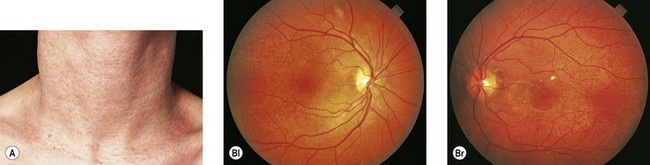

Медицинские исследования: эластическая псевдоксантома